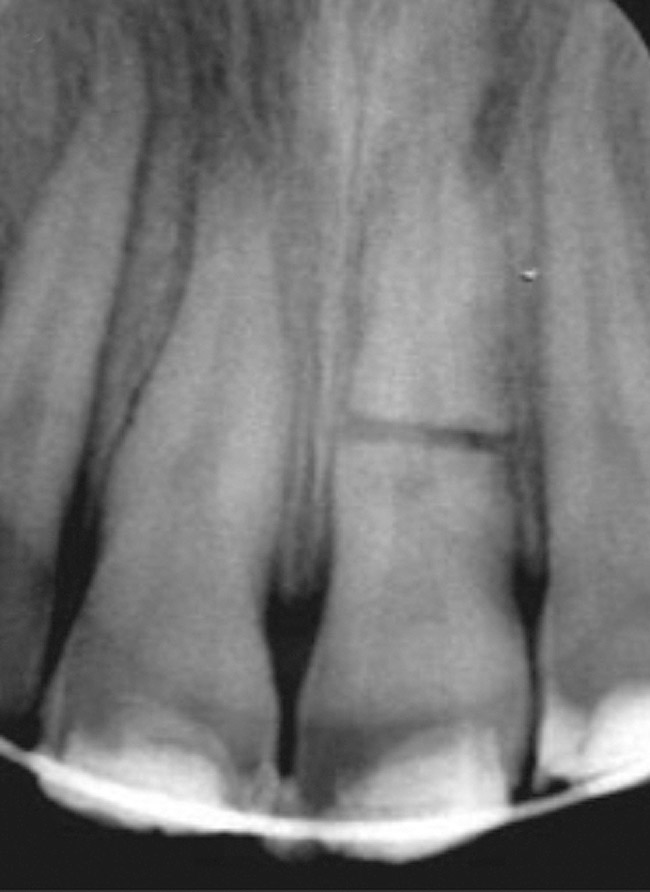

Initially, case studies appeared in the endodontic literature in which patients underwent CBCT imaging for the purposes of diagnosis20-22 and presurgical treatment planning.19 Recent reports have successfully shown the use of CBCT to locate missed canals,23 detect the extent of dentoalveolar fractures,20 identify resorption patterns,22 and compare cystic with granulomatous periapical lesions.17 Figure 2A through Figure 2C show a case in which the missed canal was suggested by periapical radiographs but confirmed with CBCT.24 Similarly in Figure 3A through Figure 3D, the additional diagnostic information attained from CBCT confirmed the diagnosis and extent of the root fracture, which initially was observed in the periapical radiographs (Figure 4A and Figure 4B).20 Notably, the extent of the lingual fracture as well as any alveolar complications could be visualized by CBCT only.

Figure 4a  Initially, the periapical radiographs showed the root fractures but not the extent of the lingual fracture or the alveolar complications (A,B).

Figure 4a

Figure 4b  Initially, the periapical radiographs showed the root fractures but not the extent of the lingual fracture or the alveolar complications (A,B).

Figure 4b